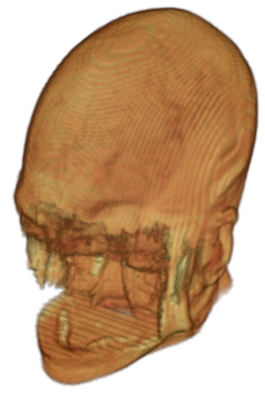

To prevent these types of attack, medical scans are currently de-identified using crude removal-based techniques [Bischoff-Grethe et al.(2007)Bischoff-Grethe, Ozyurt, Busa, Quinn, Fennema-Notestine, Clark, Morris, Bondi, Jernigan, Dale, Brown, and Fischl, Schimke et al.(2011)Schimke, Kuehler, and Hale, Milchenko and Marcus(2013)] which seek to remove privacy-sensitive parts of the head (examples in Figure 3). However, as we demonstrate, these existing techniques fail to reliably hide the patient’s identity – or they are so aggressive that they impair further medical analyses. A better solution is needed.

Benchmark De-Identification Methods. We compare our result with three publicly available and widely-established methods for de-identification of MRI head scans, depicted in Figure 3. All methods have in common that they (1) are not deep-learning-driven, (2) require no additional training and (3), are used on a day-to-day basis in neuroscience and clinical research. All procedures were applied with default settings on images of resolution . The methods include QUICKSHEAR [Schimke et al.(2011)Schimke, Kuehler, and Hale], FACE MASK [Milchenko and Marcus(2013)], and DEFACE [Bischoff-Grethe et al.(2007)Bischoff-Grethe, Ozyurt, Busa, Quinn, Fennema-Notestine, Clark, Morris, Bondi, Jernigan, Dale, Brown, and Fischl]. Descriptions of the methods are provided in the Appendix. We also include MRI WATERSHED [Ségonne et al.(2004)Ségonne, Dale, Busa, Glessner, Salat, Hahn, and Fischl], a skull-stripping method that removes everything except the brain.